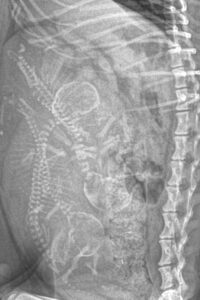

• Medical Imaging

Tullamarine Animal Hospital – Medical Imaging for Pets